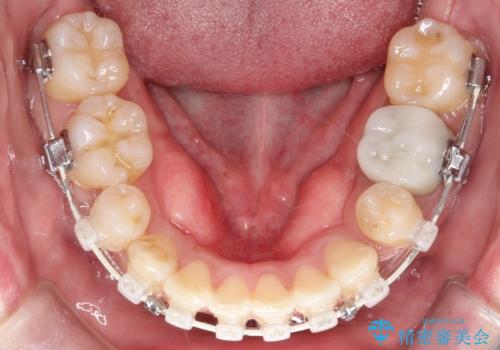

重度の叢生を抜歯矯正で改善|審美ワイヤー矯正+海外出張に伴う中断・再開対応

- 治療計画

重度の叢生により、抜歯を伴う矯正が必要と判断しました。目立ちにくい透明な審美ブラケットを用いたワイヤー矯正を実施しましたが、治療途中での海外出張が決定したため、一度矯正装置を取り外し、保定装置で現状維持を行いました。帰国後に改めて装置を装着し矯正を再開。患者様のライフスタイルに柔軟に対応しながら、最終的には理想的な歯並びと美しい口元を実現しました。